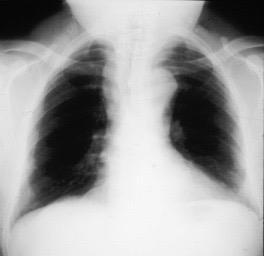

Radiografía AP en politraumatizado con enfisema subcutáneo severo.

Kumar H M,et al. Ginkgo leaf sign and subcutaneous emphysema.BMJCase Rep .2018